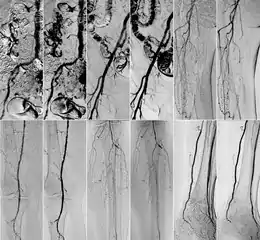

In 2018 Gyánó M. et al. compared the quality of DVA and DSA (digital subtraction angiography) images in a prospective observational crossover study, which involved the analysis of 232 image pairs of 42 patients undergoing lower limb x-ray angiography (performed by using iodinated contrast agent) between February and June 2017. Methods included the measurement of SNR (signal-to-noise ratio) and visual quality comparison.[1]

Although other factors like spatial resolution, sharpness, and object size may contribute to image quality and object perceptibility, noise places a fundamental limitation on the ability to recognize structures on low-contrast images and that was the main reason why the SNR measurement method was chosen. The results showed 2-3 times higher SNR values in the case of DVA images compared to traditionally used DSA images, which has indicated that DVA has the potential to improve the ability to view blood vessels, since a higher SNR value indicates lower noise levels.

Qualitative comparison has been performed by three vascular surgeons and three interventional radiologists, with about 17 years of experience on the average. In an online visual questionnaire, which showed DVA and DSA image pairs of the same anatomical regions, raters were asked to choose the image which they found to be more useful for making the diagnosis. Overall, the raters judged the kinetic images better in 69% of all images. Regarding different anatomical regions, the raters agreed that the DVA was significantly better for talocrural and popliteal regions.

Since the SNR is proportional to radiation dose, the authors have concluded that the higher SNR values indicate that the DVA method has the ability to generate angiographic images which have the same quality as the currently used DSA, but the dose of the administered radiation and/or contrast media could be lowered to achieve the same vessel visibility.